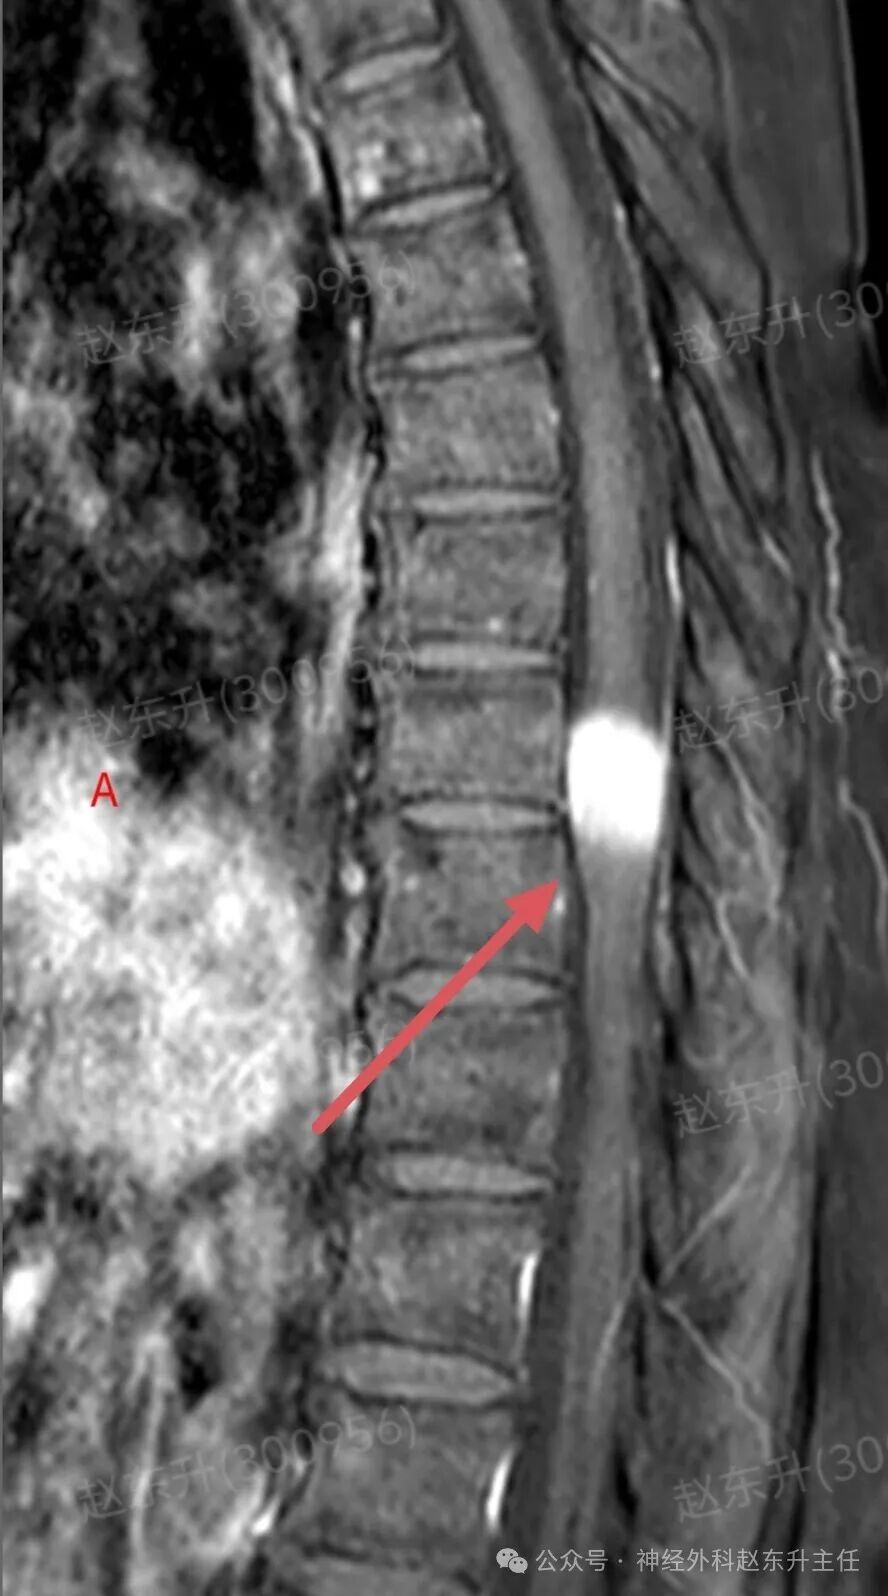

有一天门诊来了一位69岁的甘肃女性患者。因为长期腰腿疼,在多家医院就诊治疗无效,长期按摩针灸拔罐艾灸电疗磁疗腰腿疼,稍有缓解。随后又持续加重,在外院查腰椎磁共振,未见明显异常,随后在向上查胸椎磁共振,发现椎管内一个巨大肿瘤压迫脊髓比较明显。她疼痛评分有6分,夜间疼痛难忍,难以入睡。此次发现椎管肿瘤以后来到我院就医。根据胸椎磁共振的表现,考虑脊膜瘤可能。随后在全麻下,我们在显微镜下彻底切除了肿瘤组织术后患者疼痛缓解下地行走,较术前改善大小便也恢复正常了。

图片图片图片图片图片图片肌电图提示下肢神经、骶神经损伤术中切除的肿瘤组织西安市红会医院神经外科赵东升主任介绍:椎管内脊膜瘤是一种常见的、通常为良性的椎管内肿瘤,起源于覆盖脊髓和神经根的脊膜(特别是蛛网膜的“帽细胞”)。核心特征:性质:绝大多数(90%以上)为良性(WHO I级),生长缓慢。位置:可发生于椎管的任何节段,但最常见于胸椎(约占70%),其次是颈椎、腰椎少见。特点:肿瘤通常有完整的包膜,与硬脊膜基底紧密相连,像一颗“附着在墙壁上的珍珠”,可压迫脊髓和神经根,但通常不侵入神经组织本身。发病率:是椎管内最常见的肿瘤之一,约占所有椎管肿瘤的25%。好发于中年女性(女:男比例约为4:1),可能与激素水平有关。

病史与神经系统查体:医生通过询问病史和详细的神经系统检查,初步判断病变的节段和严重程度。影像学检查(确诊的关键):增强磁共振(MRI): 是诊断的金标准。典型表现:T1加权像上呈等或稍低信号,T2加权像上呈等或稍高信号;增强扫描后呈现显著的、均匀的强化。特征性的“硬脊膜尾征”(肿瘤附着处硬脊膜线状强化)具有重要诊断价值。可清晰显示肿瘤与脊髓、神经根的关系。CT扫描:可显示肿瘤是否伴有钙化(沙粒体型脊膜瘤常见),以及是否有椎体或椎弓根的骨质增生,但对软组织分辨率不如MRI。X线平片:作用有限,可能仅见椎弓根间距增宽等间接征象。